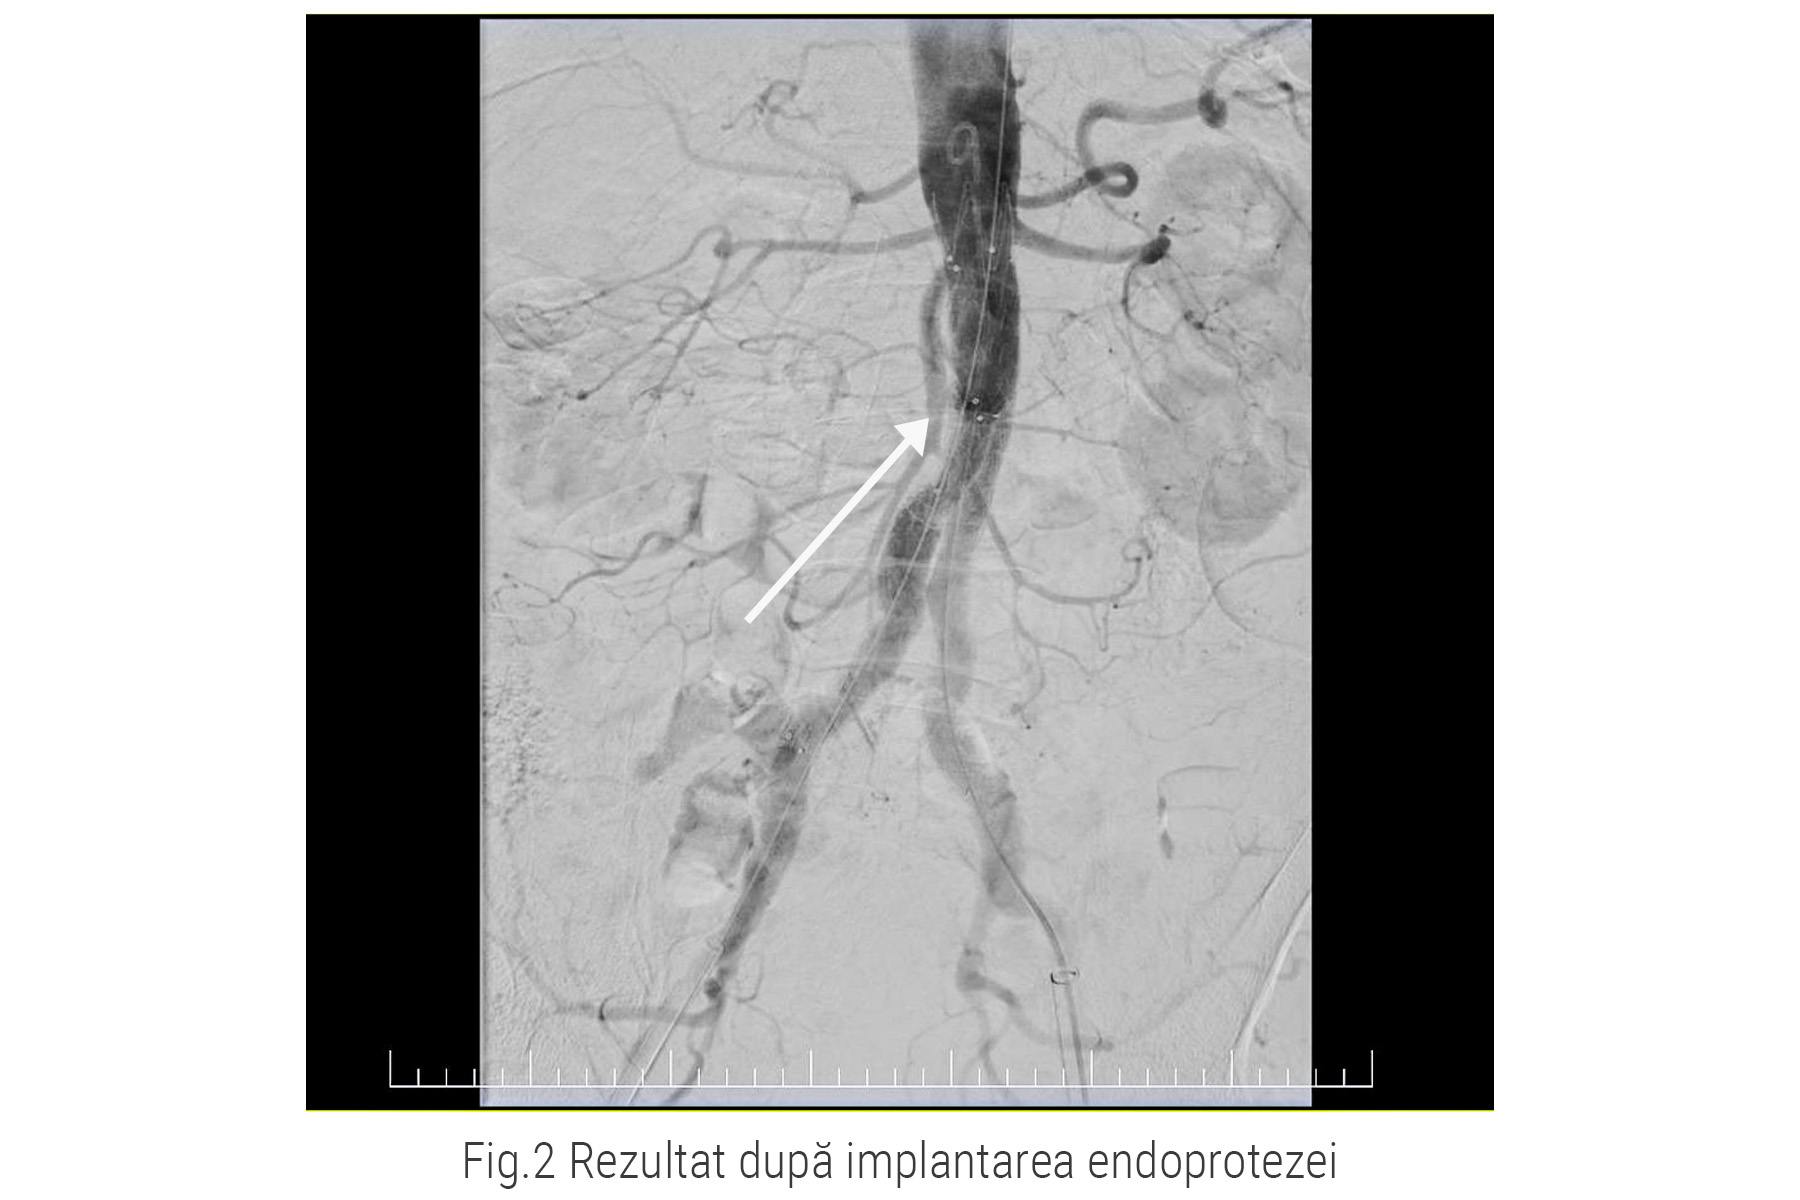

În imaginea de mai jos puteți observa imaginea angiografică după implantarea stentului-graft.

Medicii Ares au efectuat o nouă aortografie pentru a observa poziția stentului-graft și odată ce au fost mulțumiți de rezultat, au retras materialele și la locul puncțiilor au montat dispozitive Angioseal pentru realizarea hemostazei.

Ulterior, au introdus stentul-graft, în poziție colabată, strânsă și l-au direcționat prin artere până la nivelul anevrismului. Aici, prin manevre intervenționale, dispozitivul este expandat și atașat de peretele arterial.